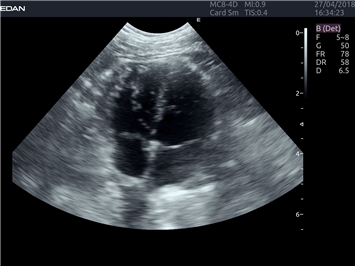

EDAN Acclarix LX4 VET представляет собой профессиональную ультразвуковую систему, специально разработанную для ветеринарных исследований. Сочетание стабильности, высокой производительности и эффективности делает эту систему идеальным выбором для современной ветеринарной практики.

• Адаптивная визуализация тканей:

• Оптимизация изображения для различных видов животных

• Улучшенная детализация структур

• Повышенная четкость изображения

• Улучшенная визуализация сложных анатомических структур